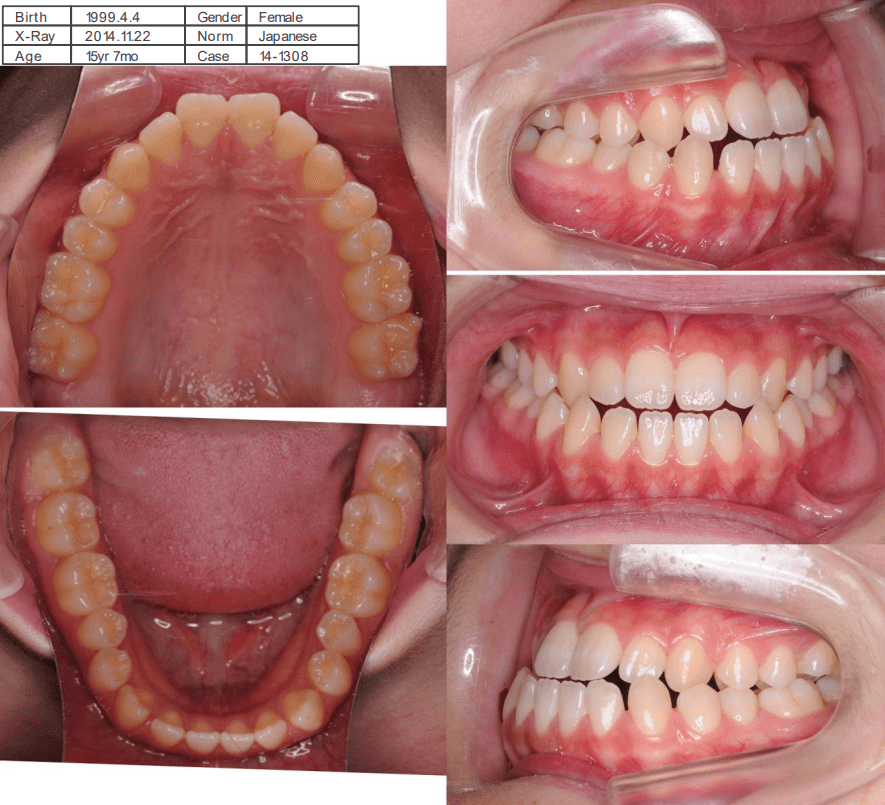

咬み合わせが逆であること(反対咬合)が気になる

| 年齢・性別 | 15歳 女性 |

|---|---|

| 主訴 | 咬み合わせが逆であること(反対咬合)を気にされて来院された女性。見た目や機能面の改善を希望されていました。 |

| 治療期間・回数 | 4年4ヶ月・28回 |

| 費用 | 900,000円 |